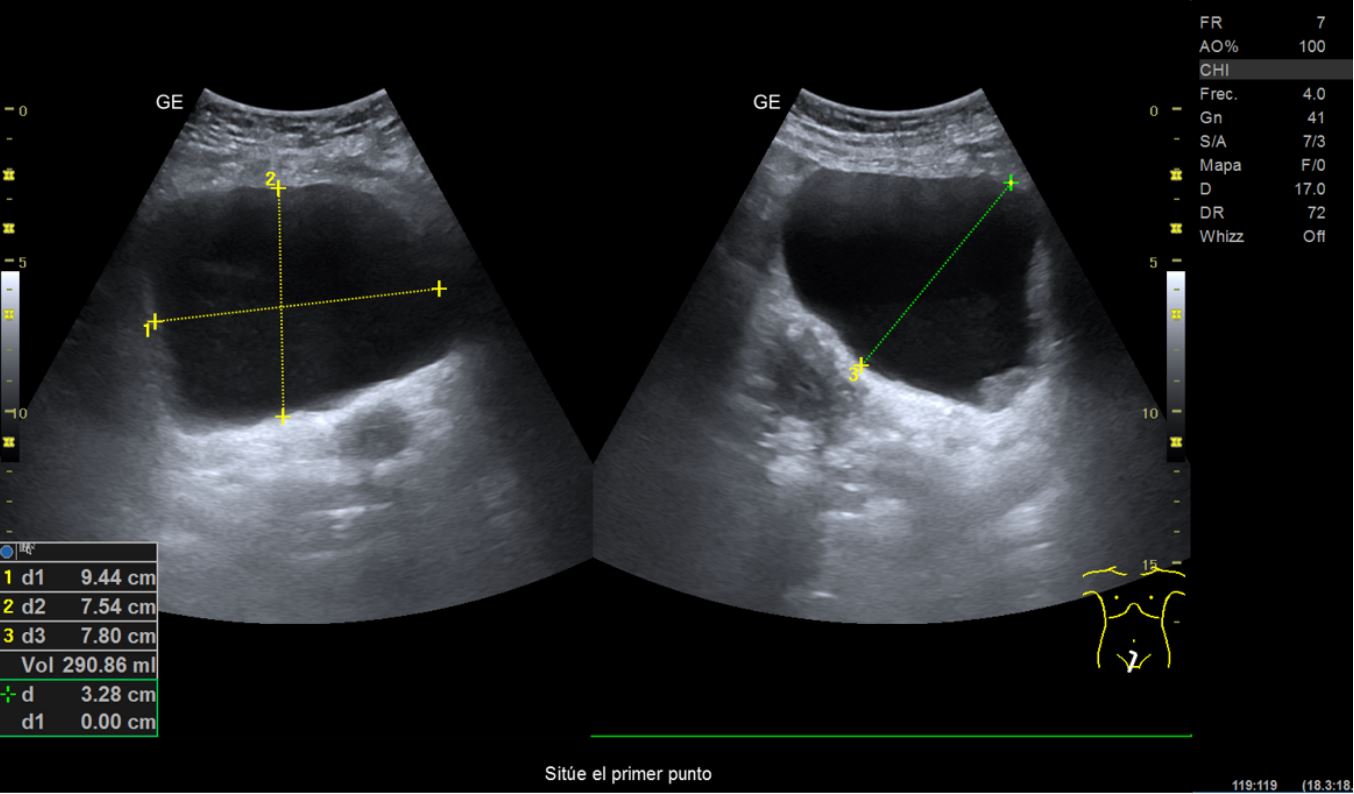

• Ecografía clínica renovesical: riñones con diámetro dentro de la normalidad. Relación cortico-medular normal. Pedículo renal Doppler normal. No se observan litiasis. Vejiga repleta, paredes finas, se observa imagen hipoecogénica en pared posterior lateral derecha que no capta señal Doppler, de unos 2,21 cm de diámetro aproximadamente. Volumen premiccional 290,86 ml, volumen posmiccional 25,54 ml.

En primer lugar se derivó a ginecología por sospecha de sangrado de origen ginecológico donde visualizan ecográficamente un grosor endometrial de 5-6 mm y realizan una biopsia endometrial con resultado de escasos fragmentos superficiales de endometrio atrófico. Tras descartar origen ginecológico y ante la persistencia del sangrado, se orienta como hematuria monosintomática y se realiza una ecografía en el centro de Atención Primaria donde se visualiza imagen hipoecogénica dependiente de la pared vesical.